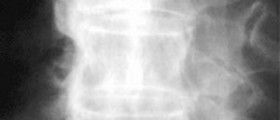

They are non-intrusive and inflict no pain, and the patient feels no discomfort in the process. We will now focus on these two devices, which are very different regarding the conditions associated with detection, but they work in the same manner and use the same technique, but each works better on different parts of the body. If you need to look at tendons, use MRI because it is better in this area, since CT provides low result in this area. MRI is best for body areas such as knee and shoulder ligaments and tendons, and this because of the ligament and tendon tissue density. Also, MRI is much better if you need images of the spinal cord due to its composition and the spinal density. The CT scan is better choice for the abnormal chest x-rays, pneumonia and cancer modality. MRI is better for the brain tumor, while CT is better in injury that causes bleeding in the brain, along with other causes of this problem. CT scan will detect organ injury, organ tear and other similar injuries that involve damaged or torn organs. The spinal cord is better seen on the MRI, while the vertebrae spinal bodies and broken bones are better seen on the CT scan. Chest cavity organs such as lungs are better seen on the CT scans, since MRI provides poor results in this department.

As we have said, the body part that needs to be visualized determines the device we use. Physics is the difference in these two imaging devices. The X-ray beam is used for the CT scan, while magnetic fields along with radio frequencies are used for the MRI, or the magnetic resonance imaging. The hydrogen molecules in the body will start spinning when MRI is used on a part of the body. The slowing down of the top will be accompanied by the wobbling of the top. Then the radio frequencies are introduced and they come into one signal frequency, which creates the image.